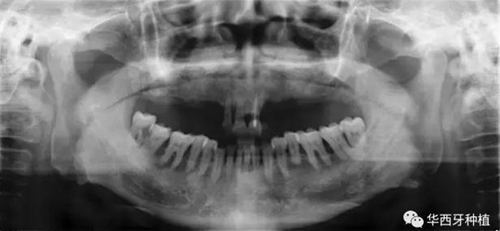

吳教授首先就全口牙缺失病種自身具有的特點,進行了總結(jié)。特別強調(diào)了嚴重的牙槽骨骨質(zhì)萎縮,其結(jié)合上下頜骨的解剖結(jié)構(gòu)(上頜竇,下齒槽神經(jīng)管)后導(dǎo)致的種植區(qū)骨量不足。

對于骨量較好的患者,選擇設(shè)計與手術(shù)方法較為簡單的傳統(tǒng)的組牙種植修復(fù),過程較為便捷,遠期效果穩(wěn)定。但是時間與經(jīng)濟成本高,并且在全口牙缺失患者口內(nèi),由于參照物較少,種植體的位置,共同就位與平行度的選擇與構(gòu)建均存在一定難度。